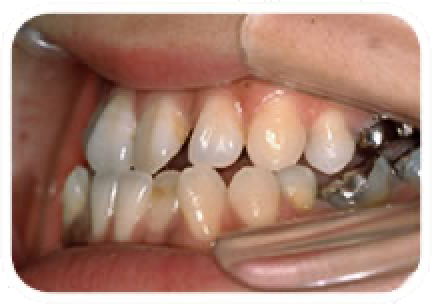

受け口(反対咬合)

上の前歯が下の前歯の後ろで噛んでいる状態です。

このままの状態が続くと年齢とともに前歯の根が傷んでくる恐れがあります。